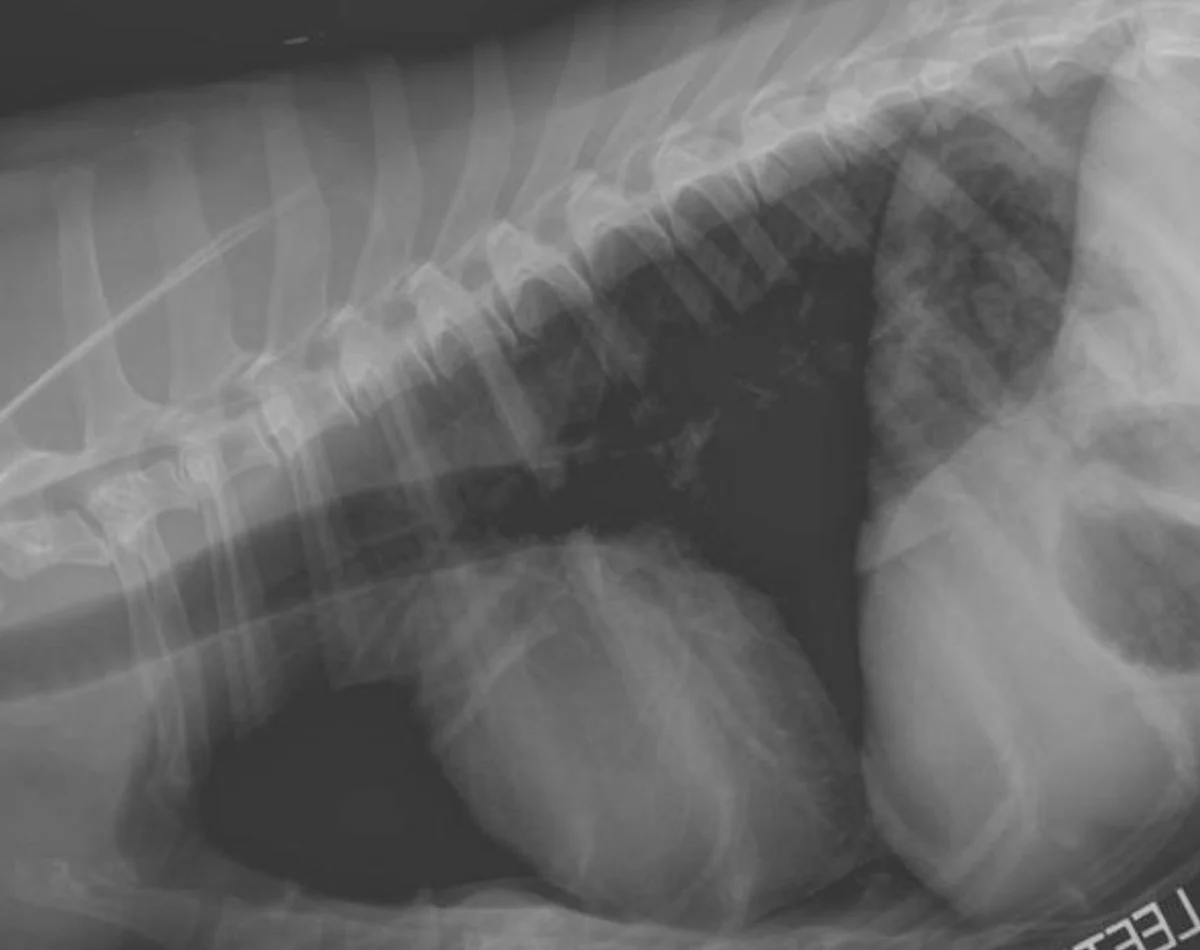

Remember to develop the films with fresh, clean developing solutions-old or exhausted developer will not work for developing technique charts. Examine the films for the setting that gives the best diagnostic quality. In Figure A, the kVp was 56, mA setting was 200, and time was 0.0125 seconds (mAs = 2.5). In this example, the bones are not easily visualized and the film overall is too white (underexposed).

In Figure B, the kVp and mA were left the same and the time was changed to 0.025 seconds (mAs = 5). In this image, the body wall, abdominal organs, and bones can all be readily visualized; this is a proper exposure. In Figure C, the kVp and mA were left the same and the time was changed to 0.05 seconds (mAs = 10). With this higher exposure technique, the ventral body wall cannot be visualized, and the abdomen is too dark (overexposed).